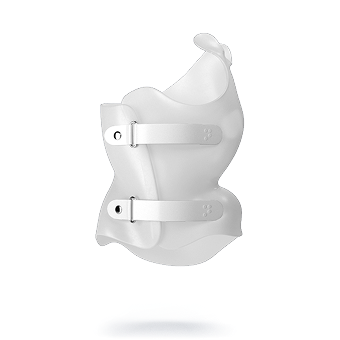

تخصيص الحزام حسب حاجة كل مريض: يتم تصميم وسائد الضغط بناءً على التحليل الثلاثي الأبعاد، لضمان توجيه القوى التصحيحية نحو مناطق الانحناء الحقيقية، بدلاً من الاعتماد على التقدير البصري فقط.

وبالتالي، يتم الجمع بين الدقة العلمية وراحة المراهق أثناء ارتداء الحزام، مما يحسن النتائج النهائية للعلاج.

- راحة استثنائية: يتميز حزام PioBrace بتصميمه الذي يوفر أقصى درجات الراحة للأطفال طوال فترة العلاج.

- سهولة الاستخدام: يمكن ارتداؤه لفترات طويلة دون التسبب في أي إزعاج للأطفال.

- موثوقية وجودة عالية: يُصنع بأحدث التقنيات لضمان أقصى درجات الراحة والكفاءة.